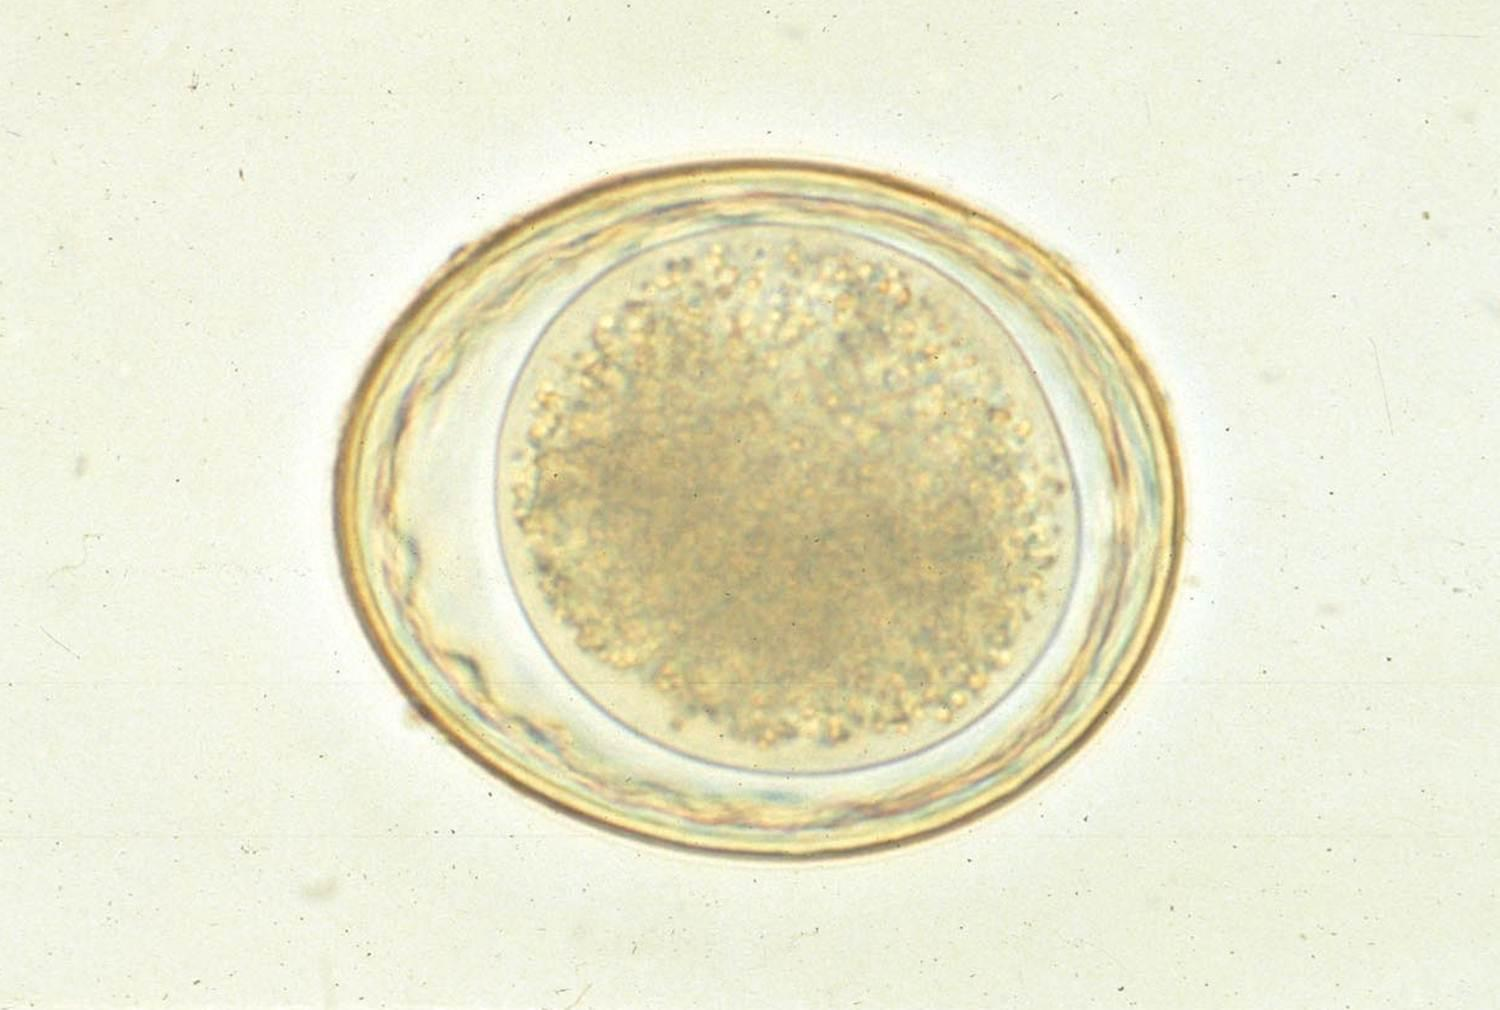

Микрофотографии яиц гельминтов Toxocara canis

Раздел: Фотоэссе